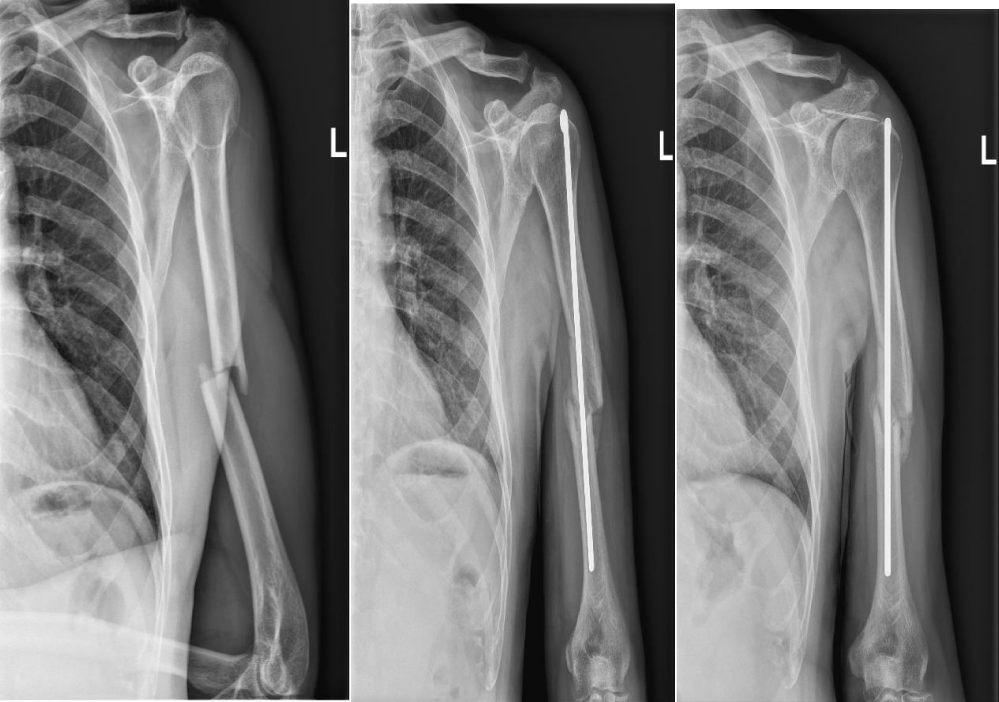

Six Examples with Different Means of Operative Treatment of Humeral Shaft Fracture

After evaluation of anatomy and biology of the fractures and backround of the patient and capabillities of further home care here are some cases we treated in a certain way with overall good bone healing status, postoperative local status, neurocirculatory status, postoperative physical terapy course and overall functional results of injured limb and good patient satisfaction (Figures 1-6).

Intramedullary nailing can offer biomechanical and surgical advantages over plating. It allows lower bending forces and better load sharing [7,11]. Patterns in which intramedullary nailing has been found to be superior are pathological and impending fractures, segmental lesions and fractures in osteopenic bone. A simple middle transverse fracture is also a good indication for intramedularry nailing. Nail inserted through a smaller incision, allows for less soft tissue stripping compared to plating techniques.